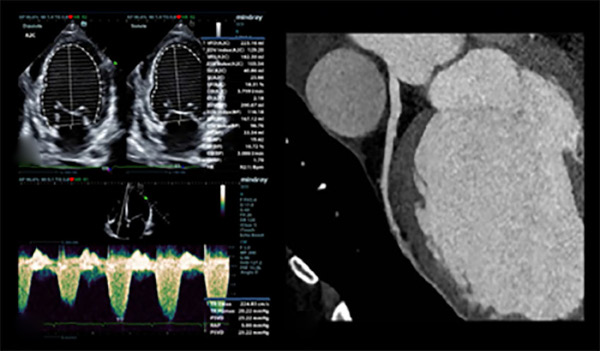

Posteriormente consulta nuevamente por guardia externa en dos oportunidades por presentar edemas en miembros inferiores, por lo cual se decide su internación para diagnóstico y control. Se hace diagnóstico clínico de insuficiencia cardiaca aguda. Se solicita ecocardiografía transtorácica, que evidencia de miocardiopatía dilatada con deterioro grave de la función ventricular, fracción de eyección ventricular izquierda (FEVI) 29 %, con hipocinesia global debido a lo cual se decide su internación en Unidad Coronaria (UCO) para estudio y tratamiento. Durante la internación se logra recabar antecedente familiar y diagnóstico genético y biopsia muscular (realizados a los seis años de edad) de distrofia muscular de Duchenne (DMD), que ha tenido seguimiento irregular y sin tratamiento médico.

En UCO se indica balance hídrico negativo; pulso de levosimendan; y se inicia tratamiento médico completo para insuficiencia cardíaca avanzada. Durante la internación se realiza ecocardiograma con medición de strain (- 14 %); angiotomografía computada coronaria con score de calcio donde no se evidencian lesiones; resonancia magnética nuclear (RMN) cardíaca con gadolinio que constata miocardiopatía dilatada con patrón de realce tardío mesocárdico que involucra el sitio de unión entre miocardio ventricular derecho e izquierdo y anteroseptal e inferoseptal, además de realce subepicárdico anterolateral e inferolateral, patrón que también se encuentra descrito en otras entidades como la miocardiopatía dilatada idiopática y la miocarditis. Además se solicita ECG Holter de 24 hs que solo evidencia extrasistolia supraventricular de baja densidad. Luego de seis días de internación, se otorga el alta sanatorial con indicación de derivación a centro de trasplante de forma ambulatoria.